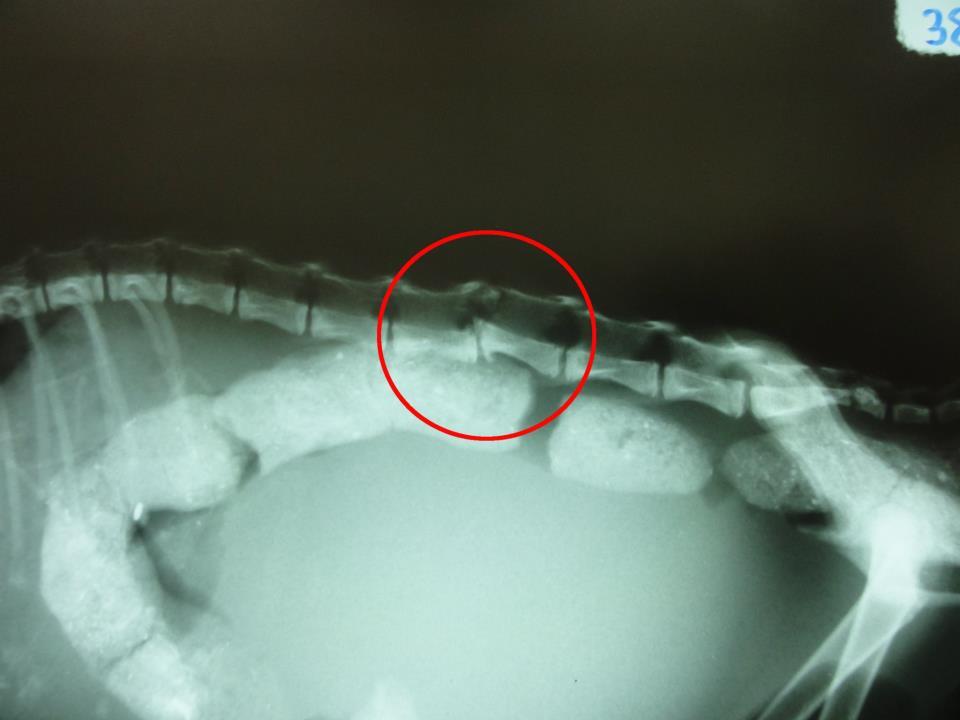

主題: 永和樂華夜市 脊椎錯位後癱貓 申請者姓名: Akimasa Tu 花色: 申請日期: 2012-10-27 00:46:50 申請者部落格: https://www.facebook.com/media/set/?set=a.431524290239137.98343.100001447087354&type=3 申請者臉書網址: https://www.facebook.com/akimasa.tu 所在縣市/合作醫院: 新北市/成蹊動物醫院 治療費用: 3100元 需求人數: 5人 已結案 (2013-06-27 13:56:38) 報名人員: Nonie Huang(已付款)、Fay Huang(已付款)、Nonie Huang(已付款)、Nonie Huang(已付款)、Nonie Huang(已付款)、 候補人員: 動物病情說明: 這貓是由一位林小姐發現,幫忙送醫,和醫師討論病情,脊椎錯位,後腿不良於行、萎縮,已一段時間,已經錯過黃金治療期,復原可能不大,無法自行大小便,所以積了一肚子大便,膀胱也都是尿,而且發炎,終身殘障需人工照護,每日擠大小便。